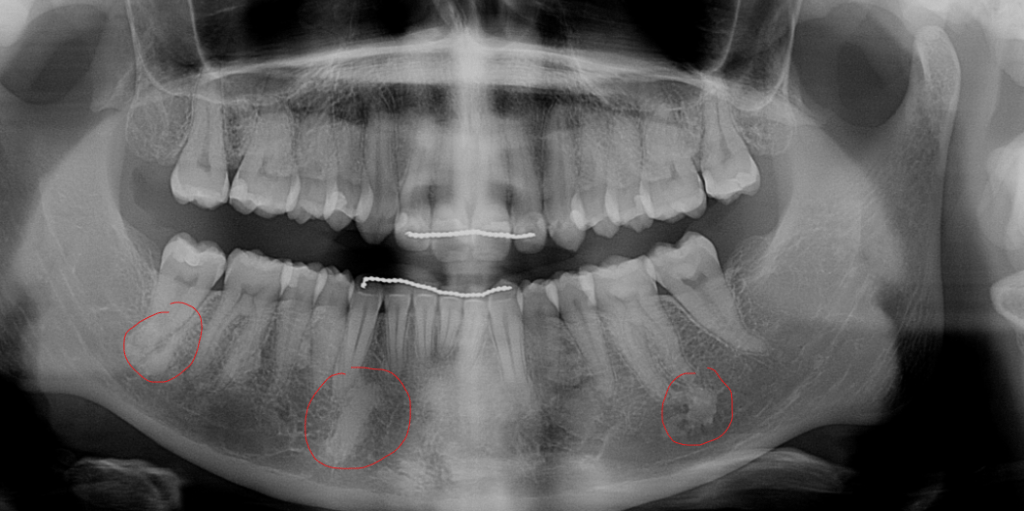

I call a dentist. The last part of me that hadn’t been checked out from bumping my head is my teeth, although I am also overdue for a check-up. I tried calling on Friday, but they were closed. They had a cancellation that day, at 1:30. Sure, why not?

The appointment went relatively smoothly. This dentist is relatively new and young, but he seems quite competent. They didn’t have time to pull my old Xrays from my old dentist to compare to my new ones. He told me I had a few cavities, so I guess that grouchy old dentist was right. He tested the two teeth that seemed to be affected by my fall and said that they weren’t dislodged or broken, but they might be dead and I might still need a root canal, but it was too early to tell.

Then he pulled up the panorama scan and my heart fell.

No…

No no no.

“I can tell by the look on your face that you know what those are. Could you tell me? I’ve never seen them before.” The dentist asks gently.

Odontoma’s, surely. I’ve never seen them either, but they can happen with my condition. I explain it to him and the hygienist writes it down so he can do more research later. The reason my teeth are rotting out and my jaw hurts. I have cancer again.

There was four, actually, but the scan he sent me didn’t have them marked, and I forgot which indistinct blob was the fourth one.

I feel kind of silly for declining the Xray in January, but I didn’t know my benefits would start all over again. It’d be nice to know how much they have grown. They certainly weren’t there during my last scan.

The dentist tells me he’s going to refer me to an oral surgeon, and send the scan to my personal email so I can send it to my oncologist. That sounds like a good plan.